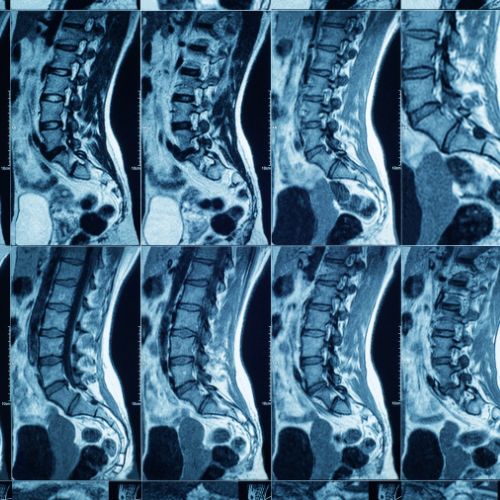

Wide Tunnel MRI Machine

Our 1.5 T MRI machine provides a convenient and comfortable scanning experience for obese and claustrophobic patients.